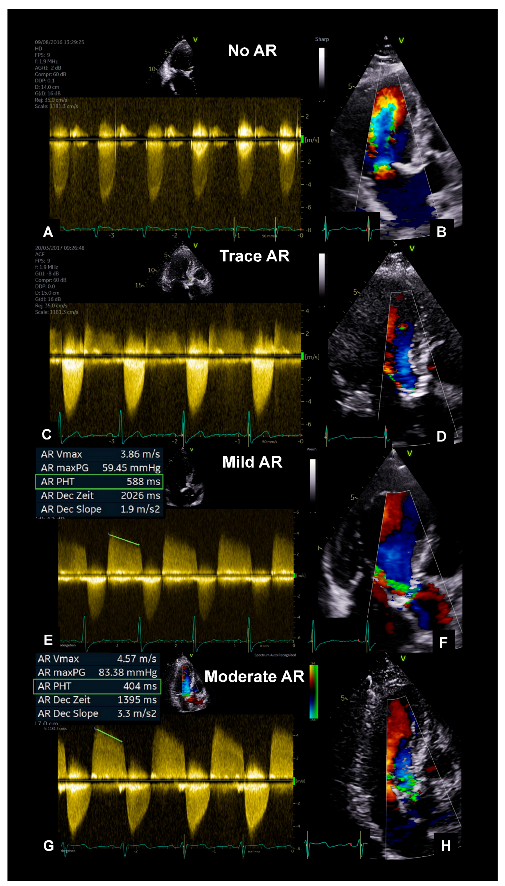

This retrospective study included 335 patients with severe AS (defined by EOA < 1 cm2 and indexed EOA < 0.6 cm2/m2) who underwent TTE and TEE at University Hospital Leipzig (Leipzig, Germany) between January 2014 and December 2017. Patients with a reduced left ventricular ejection fraction (LVEF) < 55% (n = 97) were excluded. The remaining 238 patients were divided into four subgroups, depending on AR severity, and this was determined by the pressure half time (PHT) method: no, trace, mild (PHT 500–750 ms), and moderate AR (PHT 250–500 ms) (Figure 1). Severe AS patients with severe AR (PHT < 250 ms) were not observed. Patients’ symptoms were collected from medical records.

Figure 1.

Assessment of AR in patients with severe AS. cw−Doppler spectrum and a color−coded−single frame of the apical long axis during end-diastole are illustrated for a patient with no (A,B), trace (C,D), mild (E,F), and moderate AR (G,H). Pressure half time (PHT) measured by cw−Doppler across the aortic valve along the apical long axis in mild and moderate AR (E,G). AR = Aortic regurgitation; AS = Aortic stenosis; cw = continuous wave.